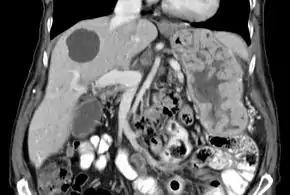

| Biopsy of the stomach in Ménétrier disease showing the substantial pit hyperplasia makes the large rugal folds appear to be covered by myriad polyps resembling hyperplastic polyps. The muscularis propria is the folded structure at the bottom center. | |

With Ménétrier disease, the stomach is characterized by large, tortuous gastric folds in the fundus and body, with the antrum generally spared, giving the mucosa a cobblestone or cerebriform (brain-like) appearance.[5] Histologically, the most characteristic feature is massive foveolar hyperplasia (hyperplasia of surface and glandular mucous cells).[3] The glands are elongated with a corkscrew-like appearance and cystic dilation is common. Inflammation is usually only modest, although some cases show marked intraepithelial lymphocytosis. Diffuse or patchy glandular atrophy, evident as hypoplasia of parietal and chief cells, is typical.[4]